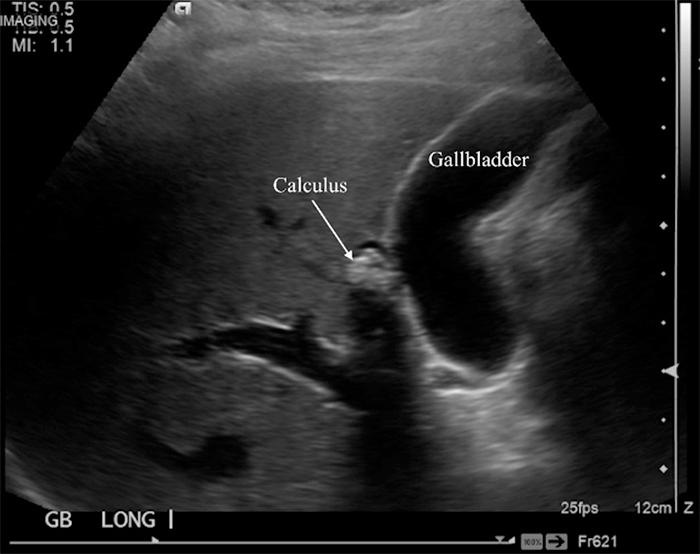

Figure 1. Abdominal Ultrasound Demonstrated Choledocholithiasis Within Presumed Right Intrahepatic Biliary Duct With Associated Duct Dilatation. Published with Permission

Her white blood cell count and liver function tests were within normal limits. Further workup showed gastritis on upper endoscopy. Her initial abdominal ultrasound from an outside facility did not detect any gallbladder anomalies but described choledocholithiasis within the right intrahepatic biliary duct with associated duct dilatation (Figure 1). These findings were subsequently confirmed with endoscopic retrograde cholangiopancreatography (ERCP); however, the stones were not retrieved out of concern for perforation and presumed need for surgical management. Following ERCP, the patient underwent magnetic resonance cholangiopancreatography (MRCP), which demonstrated an oblong, saccular gallbladder with a stone-containing accessory gallbladder or single dilated intrahepatic duct along the inferior inferomedial aspect of the right hepatic lobe, which was seen to communicate with the right hepatic duct (Figure 2).